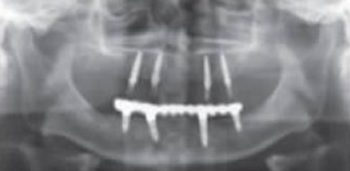

術后曲面斷層全景片(圖19)可見種植體在上頜位置較為理想,同時可見臨時義齒種植體開孔位置在13、23舌側、16、26牙合面近中,上下頜咬合關系理想。患者對種植臨時修復義齒滿意。

圖19 即刻修復后全景片